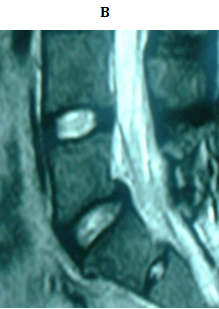

No implant failure was detected in the follow up radiographs. At the final follow up, radiological healing could be achieved bilaterally in all patients (86.6%) but four. Three of them had initial defects >3mm and one from 2-3mm, all at L5. For the healed cases, the mean time to union was 4.7 months. In the cases which did not heal, only 1 complained of significant back pain at final follow up. The other 3 did not complain of pain at final follow up (Figures 3 & 4).

Figure 3 18 years old male with bilateral pars defect at L5 underwent the procedure. (A) Preoperative lateral plain radiograph showing the defect (B) Preoperative MRI shows intact intervening disc (C, D) Immediately postoperative plain radiographs (E) CT 1 month later. Note the bone graft incorporating at the defect site.